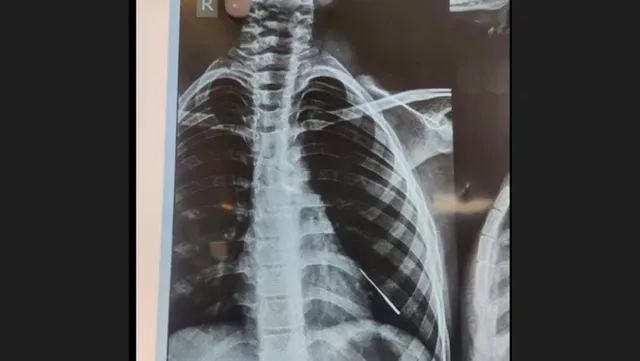

Bhubaneswar: In a remarkable and pioneering effort, the Department of Paediatrics at AIIMS-Bhubaneswar successfully saved the life of a 9-year-old boy by performing a ground-breaking bronchoscopic intervention to remove a stitching needle lodged in the lungs. This achievement marks the first instance of removing such sharp foreign bodies without resorting to open surgery in any pediatrics center in Odisha.

The young patient, hailing from West Bengal, was brought to AIIMS Bhubaneswar after aspirating a stitching needle, approximately 4 CM in length, into the left lower lobe bronchus lateral segment of the lungs. The expert team of pediatricians, including Dr. Rashmi Ranjan Das, Dr. Krishna M Gulla, Dr. Ketan, and Dr. Ramakrishna, skillfully performed bronchoscopic interventions to extract the needle without encountering any complications.